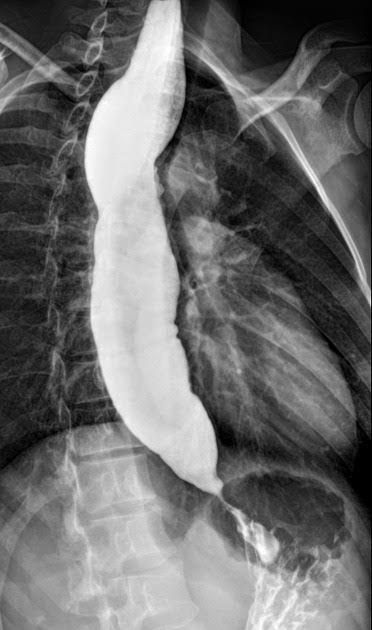

Achalasia symptoms generally appear gradually and worsen over time. Signs and symptoms may include: Inability to swallow (dysphagia), which may feel like food or drink is stuck in your throat Regurgitating food or saliva Heartburn Belching Chest pain that comes and goes Coughing at night Pneumonia (from aspiration of food into the lungs) Weight loss Vomiting